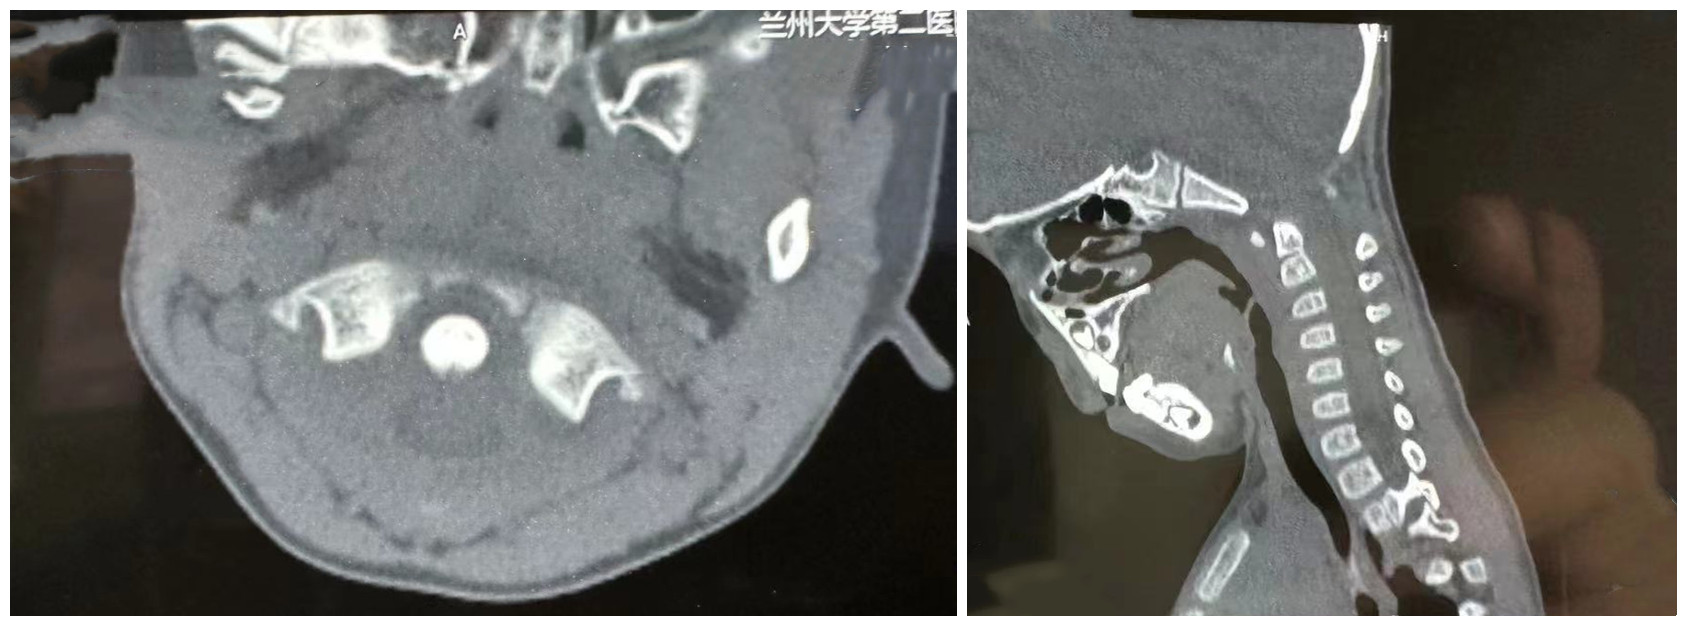

患儿术中资料

患儿因车祸导致颈部疼痛、活动时疼痛明显加重,收住骨科二病区,主诊医生根据病史情况,结合检查、检验结果及临床表现诊断为寰枢椎脱位。因患儿年幼寰枢椎钉道狭窄,周围有重要的血管、神经,常规手术方式风险较大,经讨论评估后,拟使用“O”型臂导航系统辅助进行寰枢椎脱位手术。术中患儿病情稳定,术后症状明显改善,恢复良好。

“O”型臂导航系统是全球最为先进的导航精准手术平台,由“O”型臂手术图像系统和全球最先进的Stealth Station S8手术导航系统组成。在这一系统辅助下,可使医生手术视角更广、判读脊柱状况更精确,可准确避开重要的血管、神经,使置入椎弓根螺钉的准确度更高,提高了手术的安全性,缩短了手术时间,加快了患者康复。